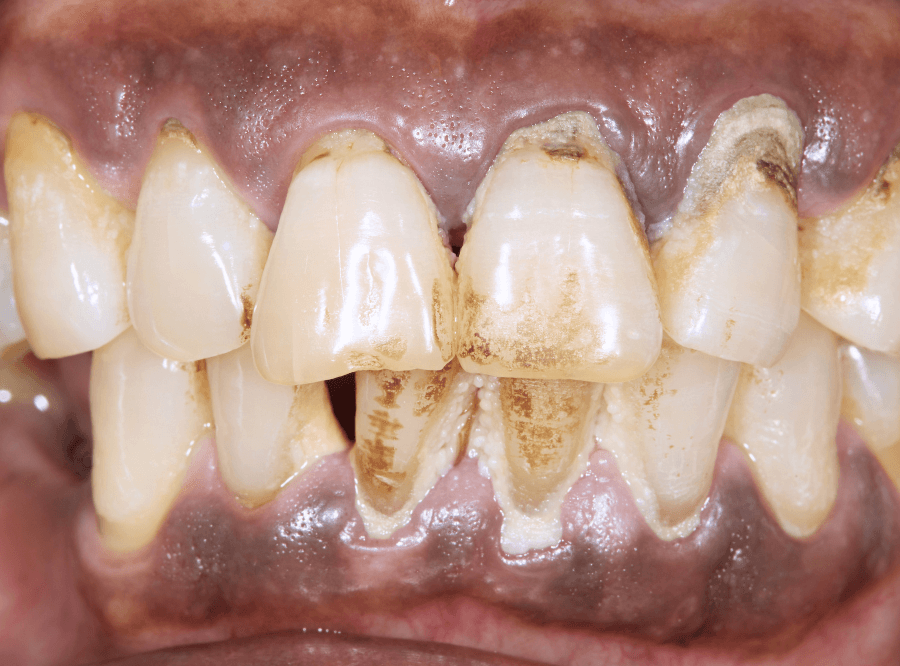

重度の歯周炎

重度歯周病は、歯を支えている骨が深くまで溶かされ、歯がグラグラと動く、最悪の場合は自然に抜け落ちてしまうような状態です。

歯周病菌がお口の中から、全身の健康にも影響を及ぼす危険性があります。

重度まで進行すると、歯を保存するのが難しくなってくる段階です。

治療は外科処置もしくは抜歯が中心になります。

症状の目安

激しい歯肉の腫れ、歯の揺れ、口臭、噛めない

治療

歯周外科、抜歯